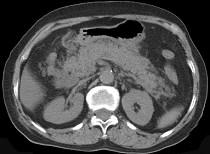

问题 男,30岁,上腹部剧痛,恶心呕吐,压痛反跳痛,血细胞计数升高,血和尿淀粉酶升高,影像表现如图,最可能的诊断是什么 ( )

选项 A.急性肠梗阻 B.胃溃疡穿孔 C.胰腺癌 D.急性胰腺炎 E.慢性胰腺炎

答案 D